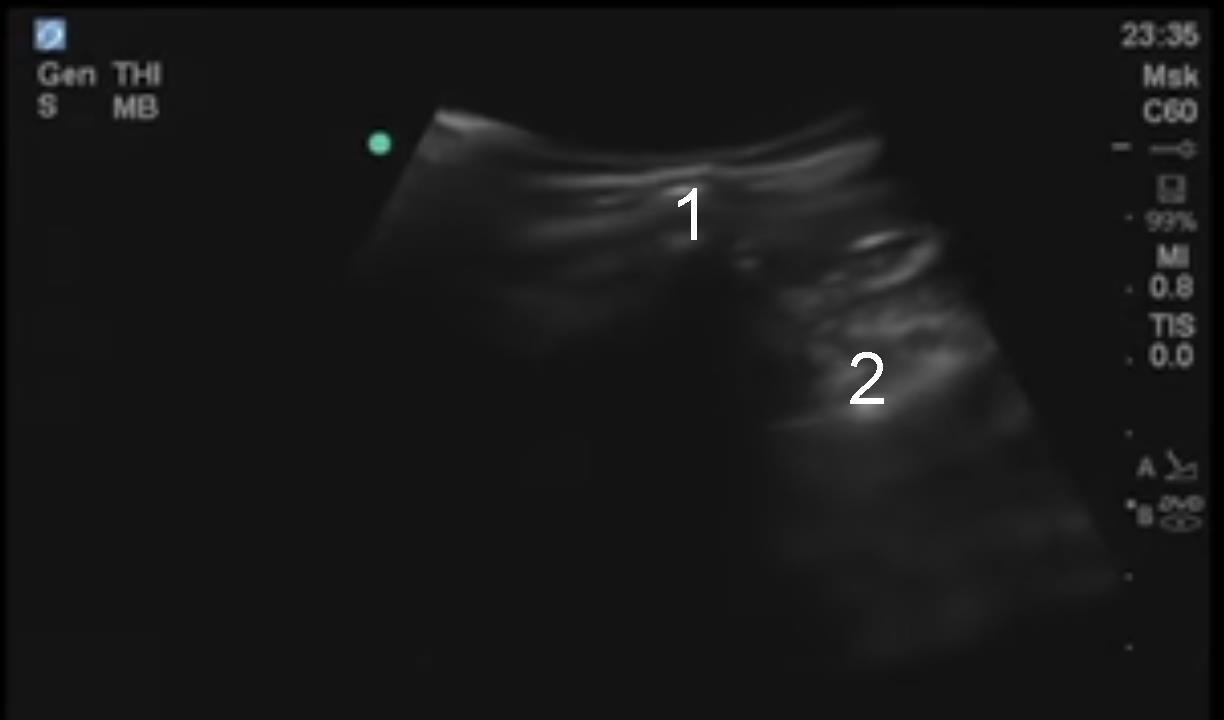

ヒップ腸骨棘と仙腸関節のイメージ

腸骨棘

仙腸関節